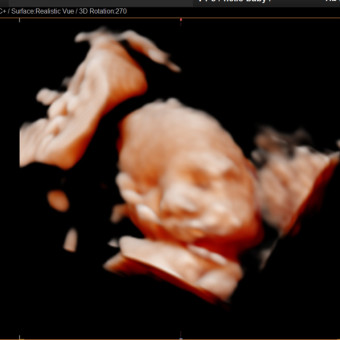

Baby Girl Castro

Alma Rubi Meza

June 15, 2026